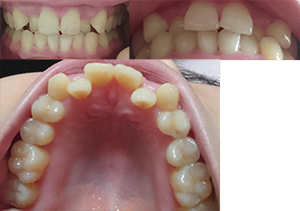

虫歯治療の為に歯医者に行ったところ、上の歯の乱杭歯?を矯正した方がいいと指摘を受けました。当方自身も後ろに下がった2本の歯はコンプレックスだったので、出来れば矯正したいです。また前歯の幅が大きいので、前歯も少し削って小さくなったらいいなと思っております。

しかし、社会人なのですが金銭的にあまり余裕がない為、可能だったら後ろに下がった2本の歯を前に出すだけの部分矯正を希望なのですが、写真を見る限り部分矯正は可能でしょうか?全体矯正は望んでおりません。

写真だけで正確な咬み合わせを判断するのは難しいですが、上の前歯は横幅(サイズ)がかなり大きい様に見えます。歯が大きいために前歯が押し合って前歯2本が内側に引っ込んだ状態になっています。

あなたの希望が、前歯がうまく並べば満足出来るなら前歯だけの部分矯正で治すことは可能と思われます。いずれにしても、気になる治したい部分の矯正を優先的に考えるべきでしょう。

部分矯正で前歯だけ矯正する場合は、抜歯する必要は有りませんが、一般的には大きな前歯を選択して、小さくする(0.4~0.8

mm程)必要があります。もちろん、痛くない範囲で削ります。

前歯だけの部分矯正で治せれば、歯を動かす期間は1年以内、もちろん外から見えない裏側(舌側)矯正で矯正可能です。

上前歯の部分矯正を選択する場合は、費用は基本料30~35万円、装置料0~15万円の合計となり、チエック料もいれて総額35~55万円程度になります。

装置料はメタル装置が0円、セラミック装置が5万円、裏側(舌側)矯正は15万円になります。